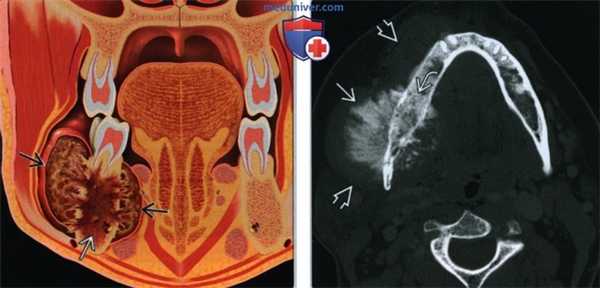

(Слева) На рисунке во фронтальной плоскости показана остеосаркома нижней челюсти справа с мягкотканным компонентом, перфорирующим кортикальный слой и распространяющимся за ее пределы, а также интрамедуллярная часть опухоли.

(Справа) При аксиальной КТ в коаном окне визуализируется большое и плотное объемное образование в нижней челюсти справа, содержащее остеоидный матрикс и вызывающее периостальную реакцию. Классическая периостальная реакция при остеосаркоме проявляется возникновением оссифицированных «тяжей», располагающихся перпендикулярно краю кости. Костный мозг в пораженных отделах нижней челюсти склерозирован. Обратите также внимание на мягкотканное объемное образование возле нижней челюсти.3. КТ при остеосаркоме верхней и нижней челюсти: